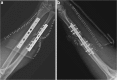

Treatment of a segmental defect in open radial and ulnar shaft fractures using rhBMP-2 and iliac crest bone graft: a case report